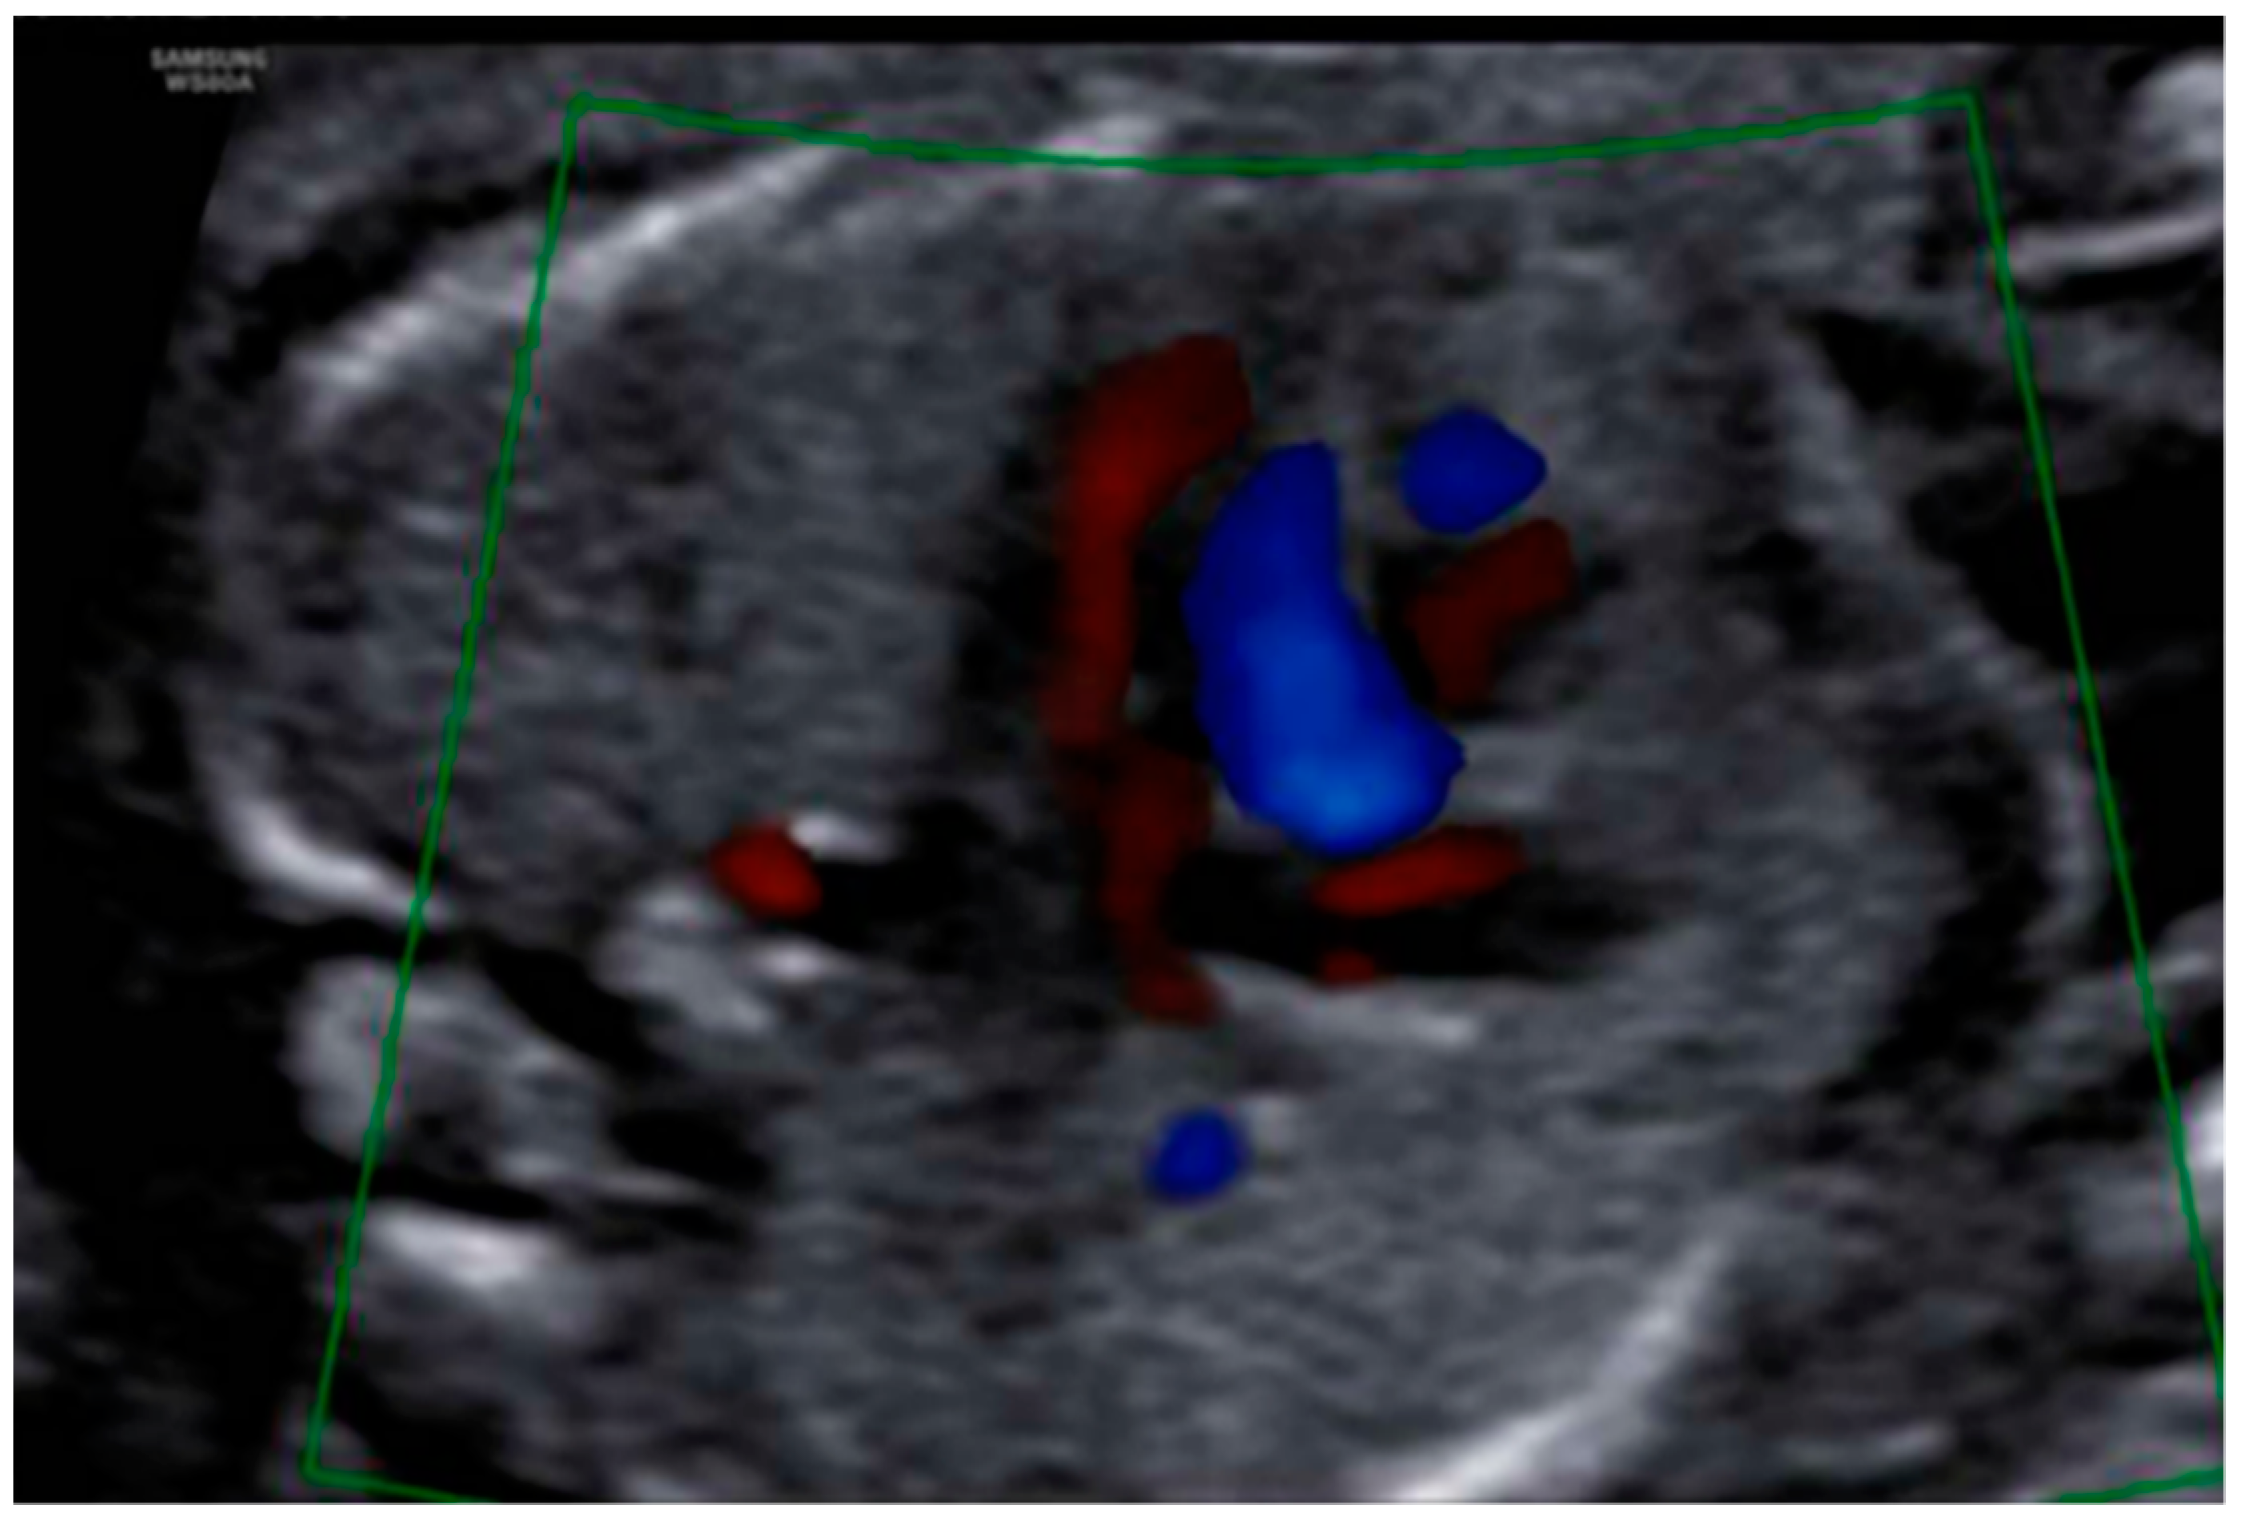

3. Results: Case Presentation

| Cardiopathy | 6% | No | No |